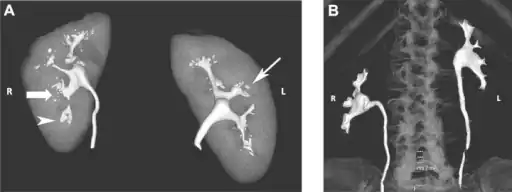

a)Bilateral papillary necrosis b)appearance of a normal papilla -